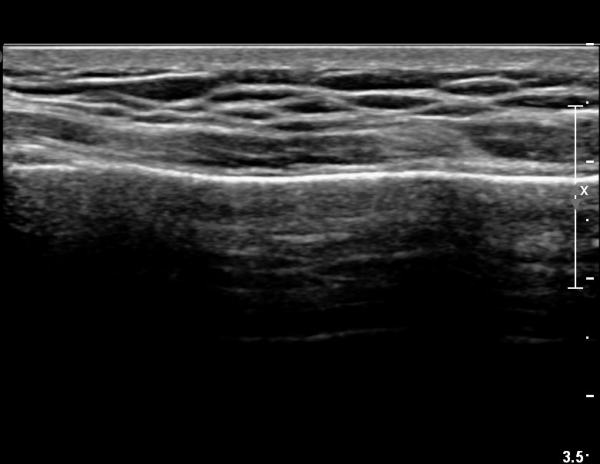

ÃÊÀ½ÆÄ °Ë»ç : ¼Õ¸ñ ¼ö±Ù°ü ±ÙÀ§ºÎ Ⱦ´Ü¸é°Ë»ç¿¡¼­ Äá¾Ë»À Ç¥ÃþÀ¸·Î ¾à°£ÀÇ ¿¬ºÎÁ¶Á÷ ºÎÁ¾ÀÌ °üÂûµÊ(»çÁø 1).

ŽÃËÀÚ¸¦ ¾à°£ ¸»´ÜÀ¸·Î À̵¿ÇÏ´Ï ¿¬ºÎÁ¶Á÷ ºÎÁ¾ÀÌ ´õ¿í ½ÉÇÏ°Ô °üÂûµÇ°í(»çÁø 2),